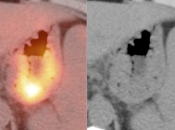

False Positives:

• Normal Physiologic Uptake: This is, far and away, the most common etiology of diffuse or segmental gastric uptake, even if very intense.

• Inflammation/Gastritis: Can be diffuse or focal.

• Gastric Ulcer: May present as a small focus of intense uptake. Will require evaluation with upper endoscopy.

• Hiatal Hernia: Increased metabolic activity is frequently encountered within a hiatal hernia. Such uptake is nearly always physiologic or inflammatory. Malignancy, however, sometimes cannot be excluded and upper endoscopy may be required.